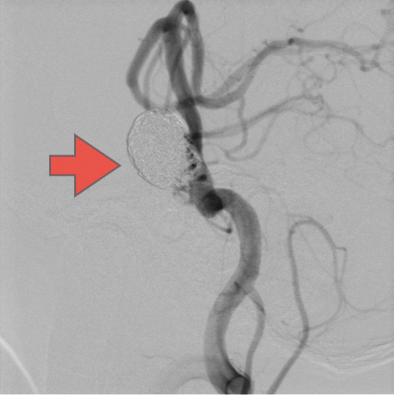

当科で治療した年々大きくなった大型脳底動脈瘤の3次元脳血管撮影像です。脳動脈瘤と周囲の血管の状態が非常によく分かるため、術前に十分な検討が可能でした。

正常の脳底動脈の血流は維持されている。